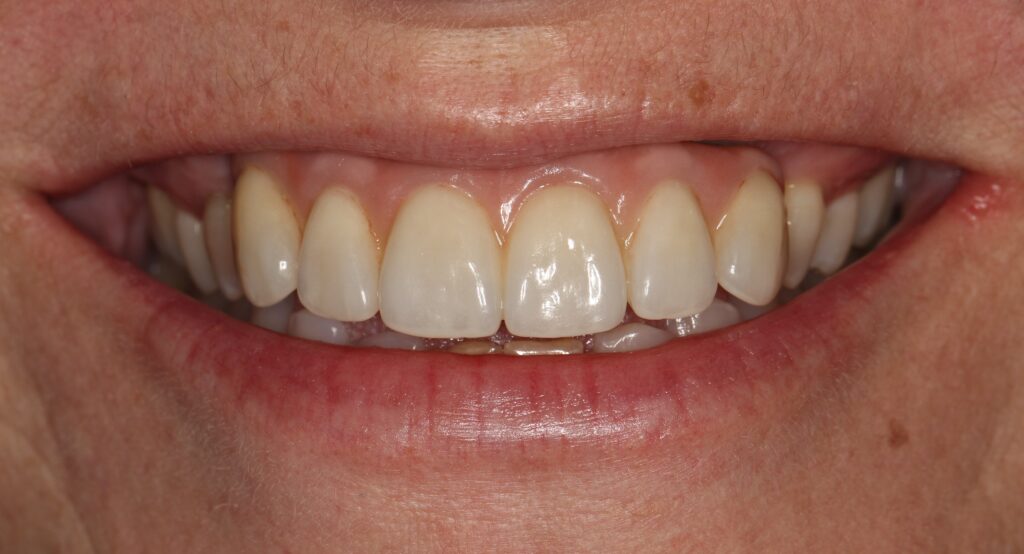

A selection of partial arch fixed implant bridge patients